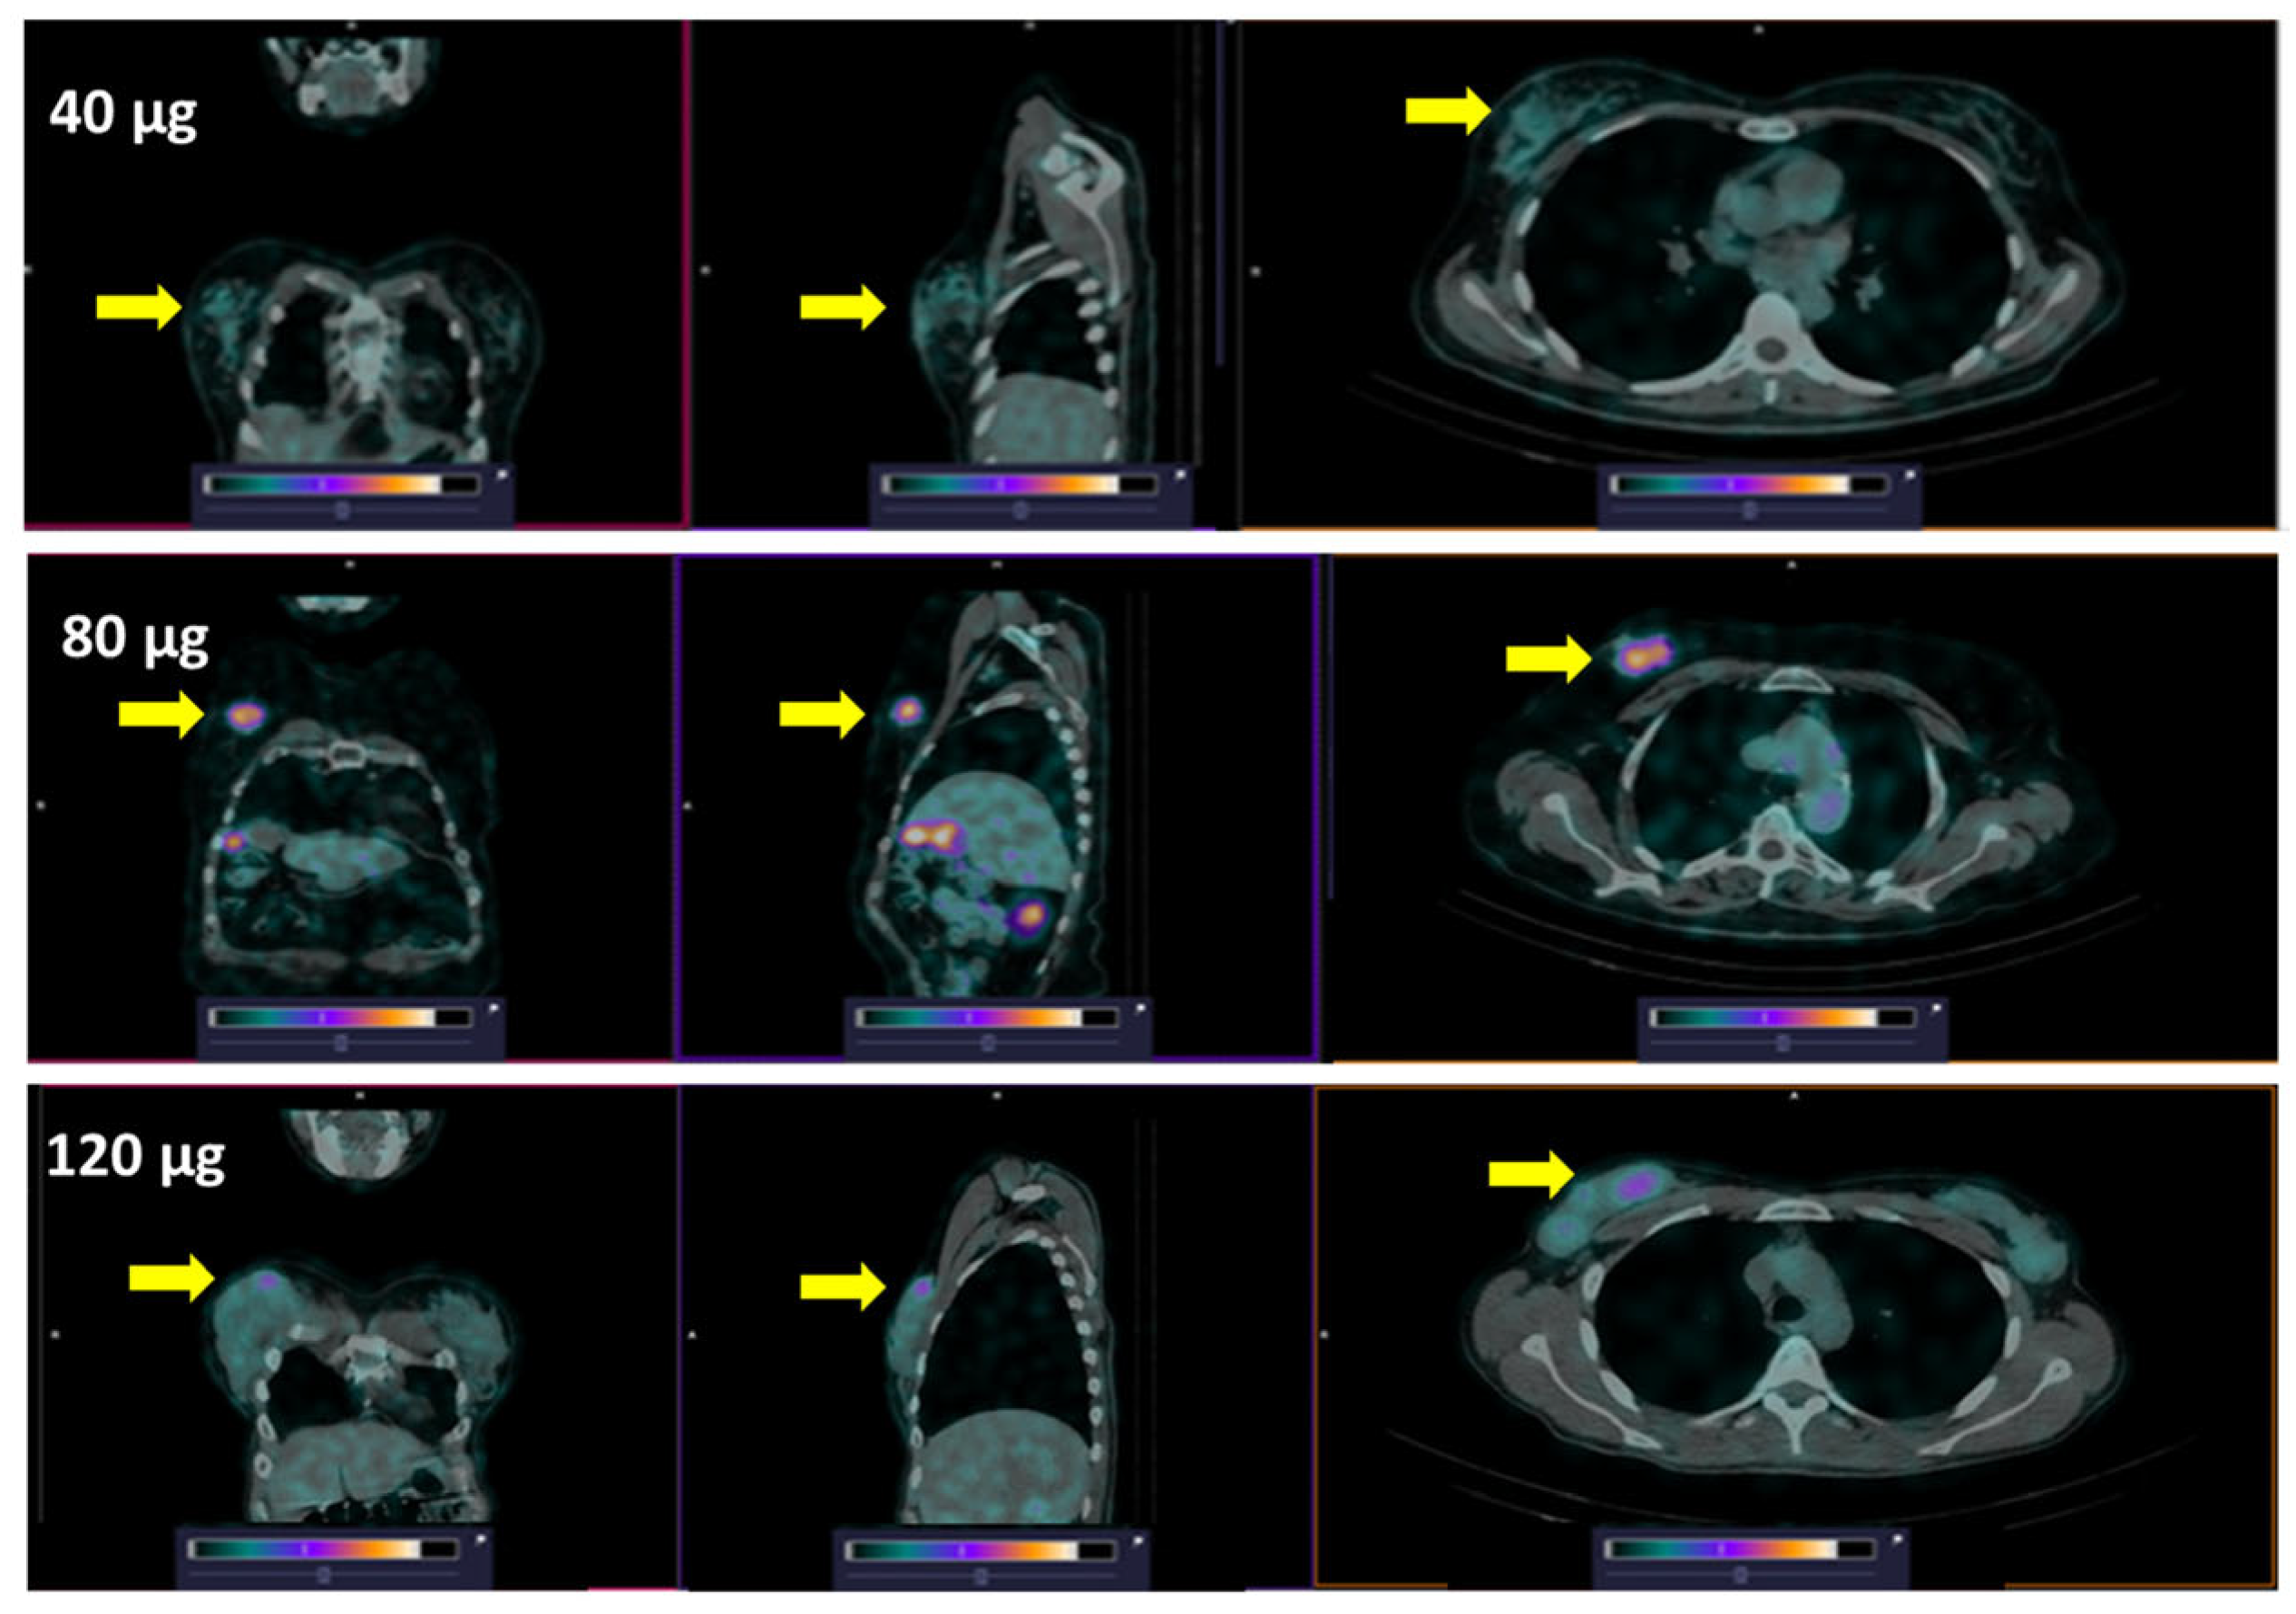

3. Results